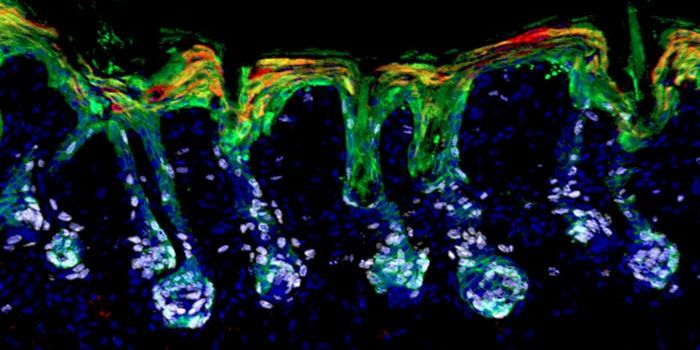

SEP 02, 2024Cell & Molecular BiologyOur skin is a crucial, protective barrier that is considered to be a major part of our immune defenses. When pathogens t ...